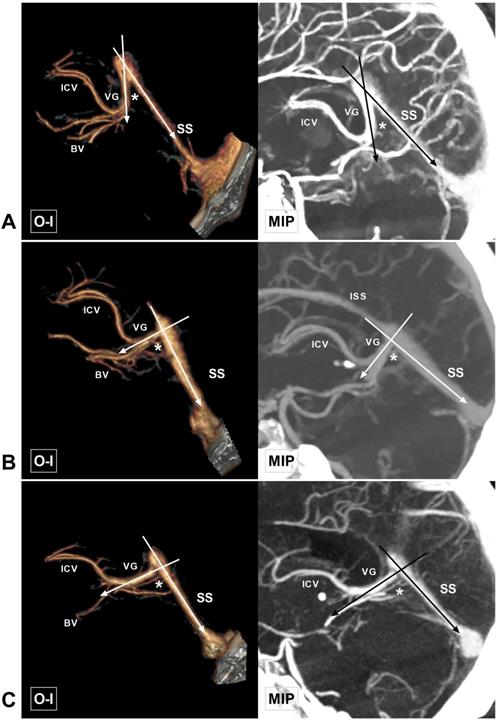

Figure 4

Different angles at the VG and SS transition area. A, CTA and MIP show an acute angle at the VG and SS transition area (asterisk). B, CTA and MIP show a right angle at the VG and SS transition area (asterisk). C, CTA and MIP show an obtuse angle at the VG and SS transition area (asterisk). Abbreviations: BV, basal vein; CTA, computed tomography angiography; ICV, internal cerebral vein; ISS, inferior sagittal sinus; MIP, maximum intensity projection; O-I, outside to inside; SS, straight sinus; VG, vein of Galen.

The length of the VG could be measured in 88 (88%, 88/100) cases, ranging from 1.5 to 41.8 mm (9.30 ± 4.76 mm). The width and thickness of the VG termination point could be measured in 74 cases, with widths ranging from 0.8 to 6.8 mm (2.89 ± 1.07 mm) and thicknesses ranging from 1.4 to 8.8 mm (3.75 ± 1.56 mm). The thickness and width of the beginning of the SS ranged from 1.1 to 6.3 mm (3.08 ± 0.94 mm) and 1.2 to 10 mm (5.55 ± 1.88 mm), respectively. The length of the SS ranged from 30.2 to 57.8 mm (43.6 ± 6.37 mm). The angle at the VG and SS transition area ranged from 25.4 to 110.6° (77.2 ± 18.0°), among which 57% (57/100) were acute angles, 31% (31/100) were right angles, and 12% (12/100) were obtuse angles (Figure 9C). The measurement data are summarized in Table 1.